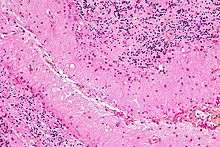

Micrograph showing Bergmann gliosis. H&E stain.

Bergmann gliosis is hyperplasia of Bergmann glia (in the cerebellum) due to Purkinje cell death,[1] as may occur in a hypoxic-ischemic insult or peritumoral compression.